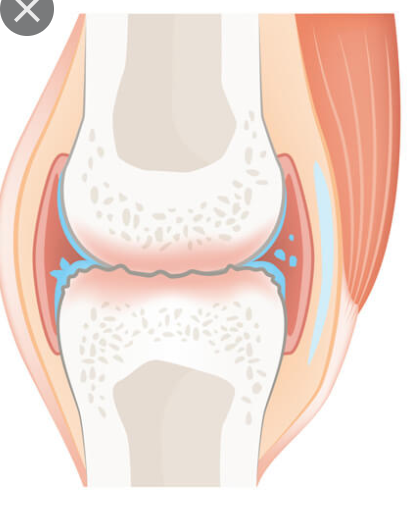

Osteoarthritis is defined as "A type of arthritis that occurs when flexible tissue at the ends of bones wears down.

The wearing down of the protective tissue at the ends of bones occurs gradually and worsens over time. It causes symptoms such as joint pain in the hands, neck, lower back, knees, or hips"

When a person has osteoarthritis, which part of a synovial joint is being worn down?

Tennis elbow is defined as: "Inflammation of the fluid-filled pads that act as cushions at the joints.

It often occurs in people that perform frequent repetitive motion. Symptoms include pain, swelling, and stiffness. Treatment includes rest, ice, and pain relievers. Surgery is rarely needed."

Which part of a synovial joint is inflamed when a person has tennis elbow?

Johnny is running at soccer practice and all of a sudden falls down in pain. He is brought into the athletic trainer. The trainer describes his condition as "You have a tear in your knee joint that has resulted in overstretching of the tissue that holds your femur bone and tibia together. "

Which part of a synovial joint did Johnny injur?

Which of the following is shown in the joint below?